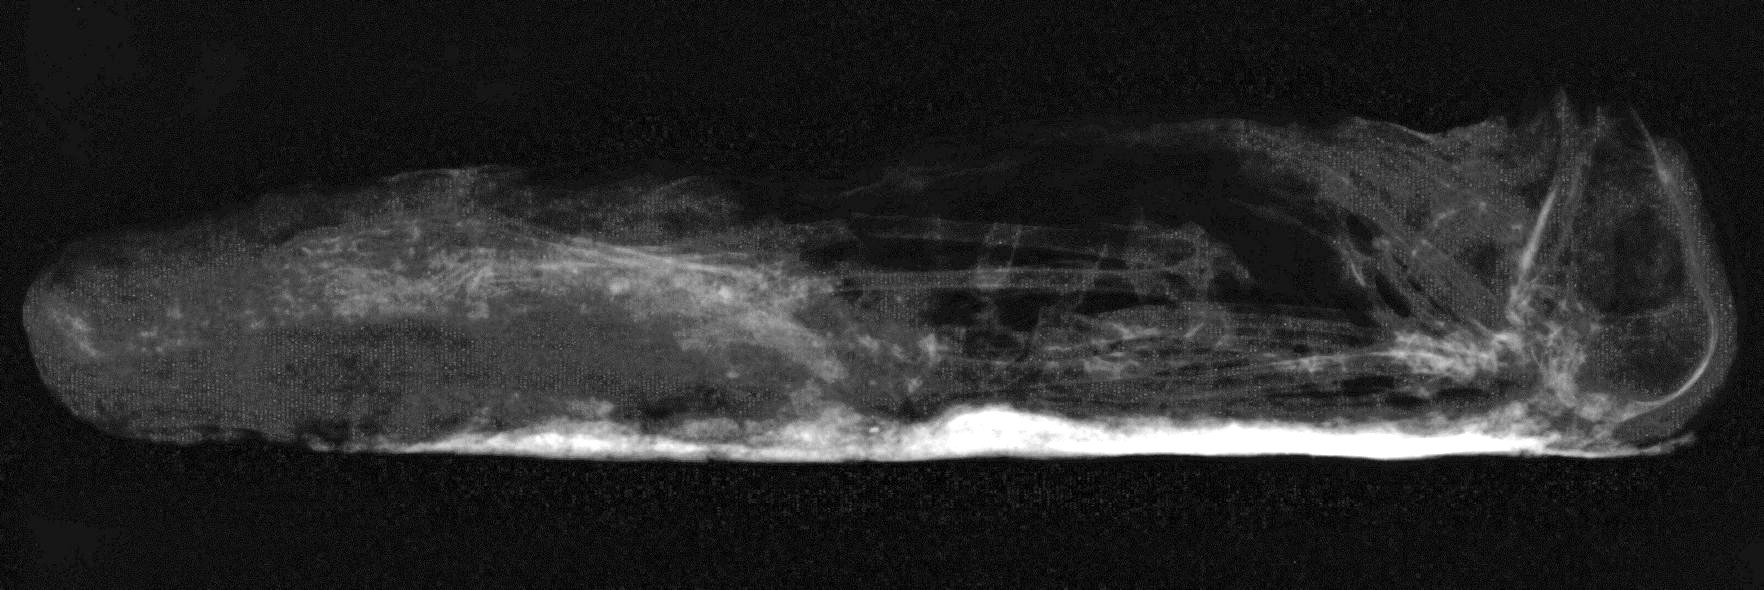

Anointment methods, attributed to resinous substances that adhered to the bird during mummification, were observed as radiodense areas. These were visible in different ways: as a complete coating around the corpse (see Figure 3); or in patches, indicative of the resin1 settling in a particular area, synonymous with the final resting position, within the wrappings before becoming completely dry (Atherton 2012; McKnight 2010) (See Figure 4).